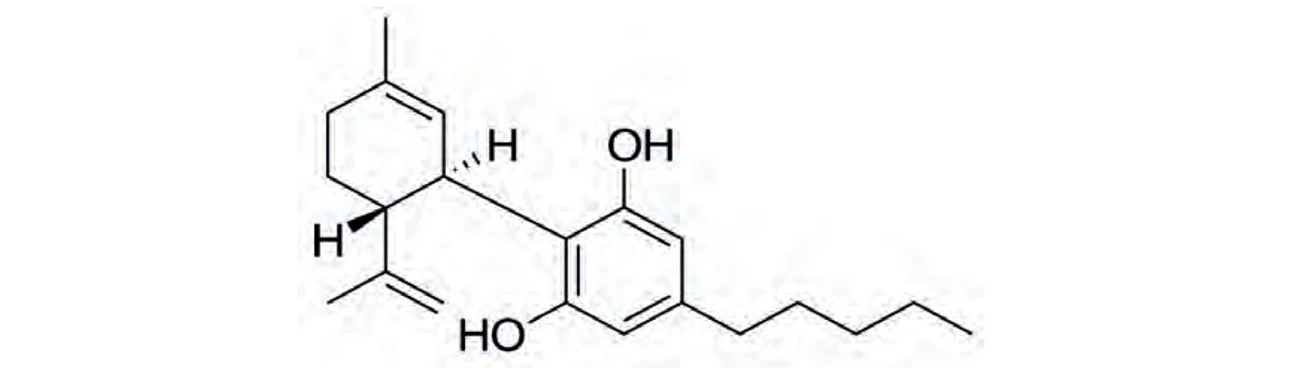

PČR: Δ9-trans-tetrahydrokanabinol (THC) – byl objeven v roce 1964 Gaonim a Mechoulamem, jedná se o psychoaktivní kanabinoid (10), rozpustnost ve vodě je 2,8 mg/l při 298,15 K (14)

PČR: Δ9-trans-tetrahydrokanabinol (THC) – byl objeven v roce 1964 Gaonim a Mechoulamem, jedná se o psychoaktivní kanabinoid (10), rozpustnost ve vodě je 2,8 mg/l při 298,15 K (14)

PČR: Kanabidiol (CBD) – nemá psychotropní účinky (13)

PČR: Kanabidiol (CBD) – nemá psychotropní účinky (13)